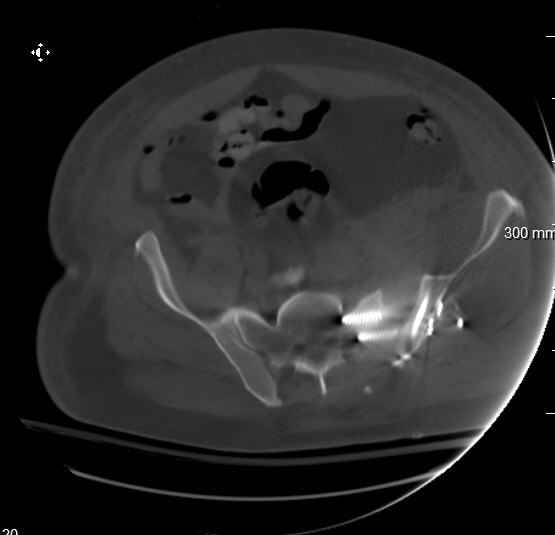

Re: APC III pelvis fx

On 11/29 took patient back to OR and explored both his anterior and posterior wounds, removed loose illiosacral screws. Left behind the screws fixing illiac crescent. Found anterior wound clean and closed it. Found posterior wound with moderate seroma and some adjacent fat necrosis. Thus far, cultures negative, but not kidding myself on that fact. Wound VAC placed and going back tomorrow to reexamine wound and may close it or re-VAC one more time. Fixator remains in place.

My plan to revise fixation is in line with your suggestion - plate symphysis and anterior approach to SI joint. It appears from post - failure CT scan that the path of the more cephalad IS screw may be helpful to place a longer screw to engage opposite illiac wing as an option, or just anterior SI plates. not likely to do this tomorrow as he remains in a fragile clinical situation regarding his pulmonary status, and profound edema/induration around his pelvis/abdomen and thighs.